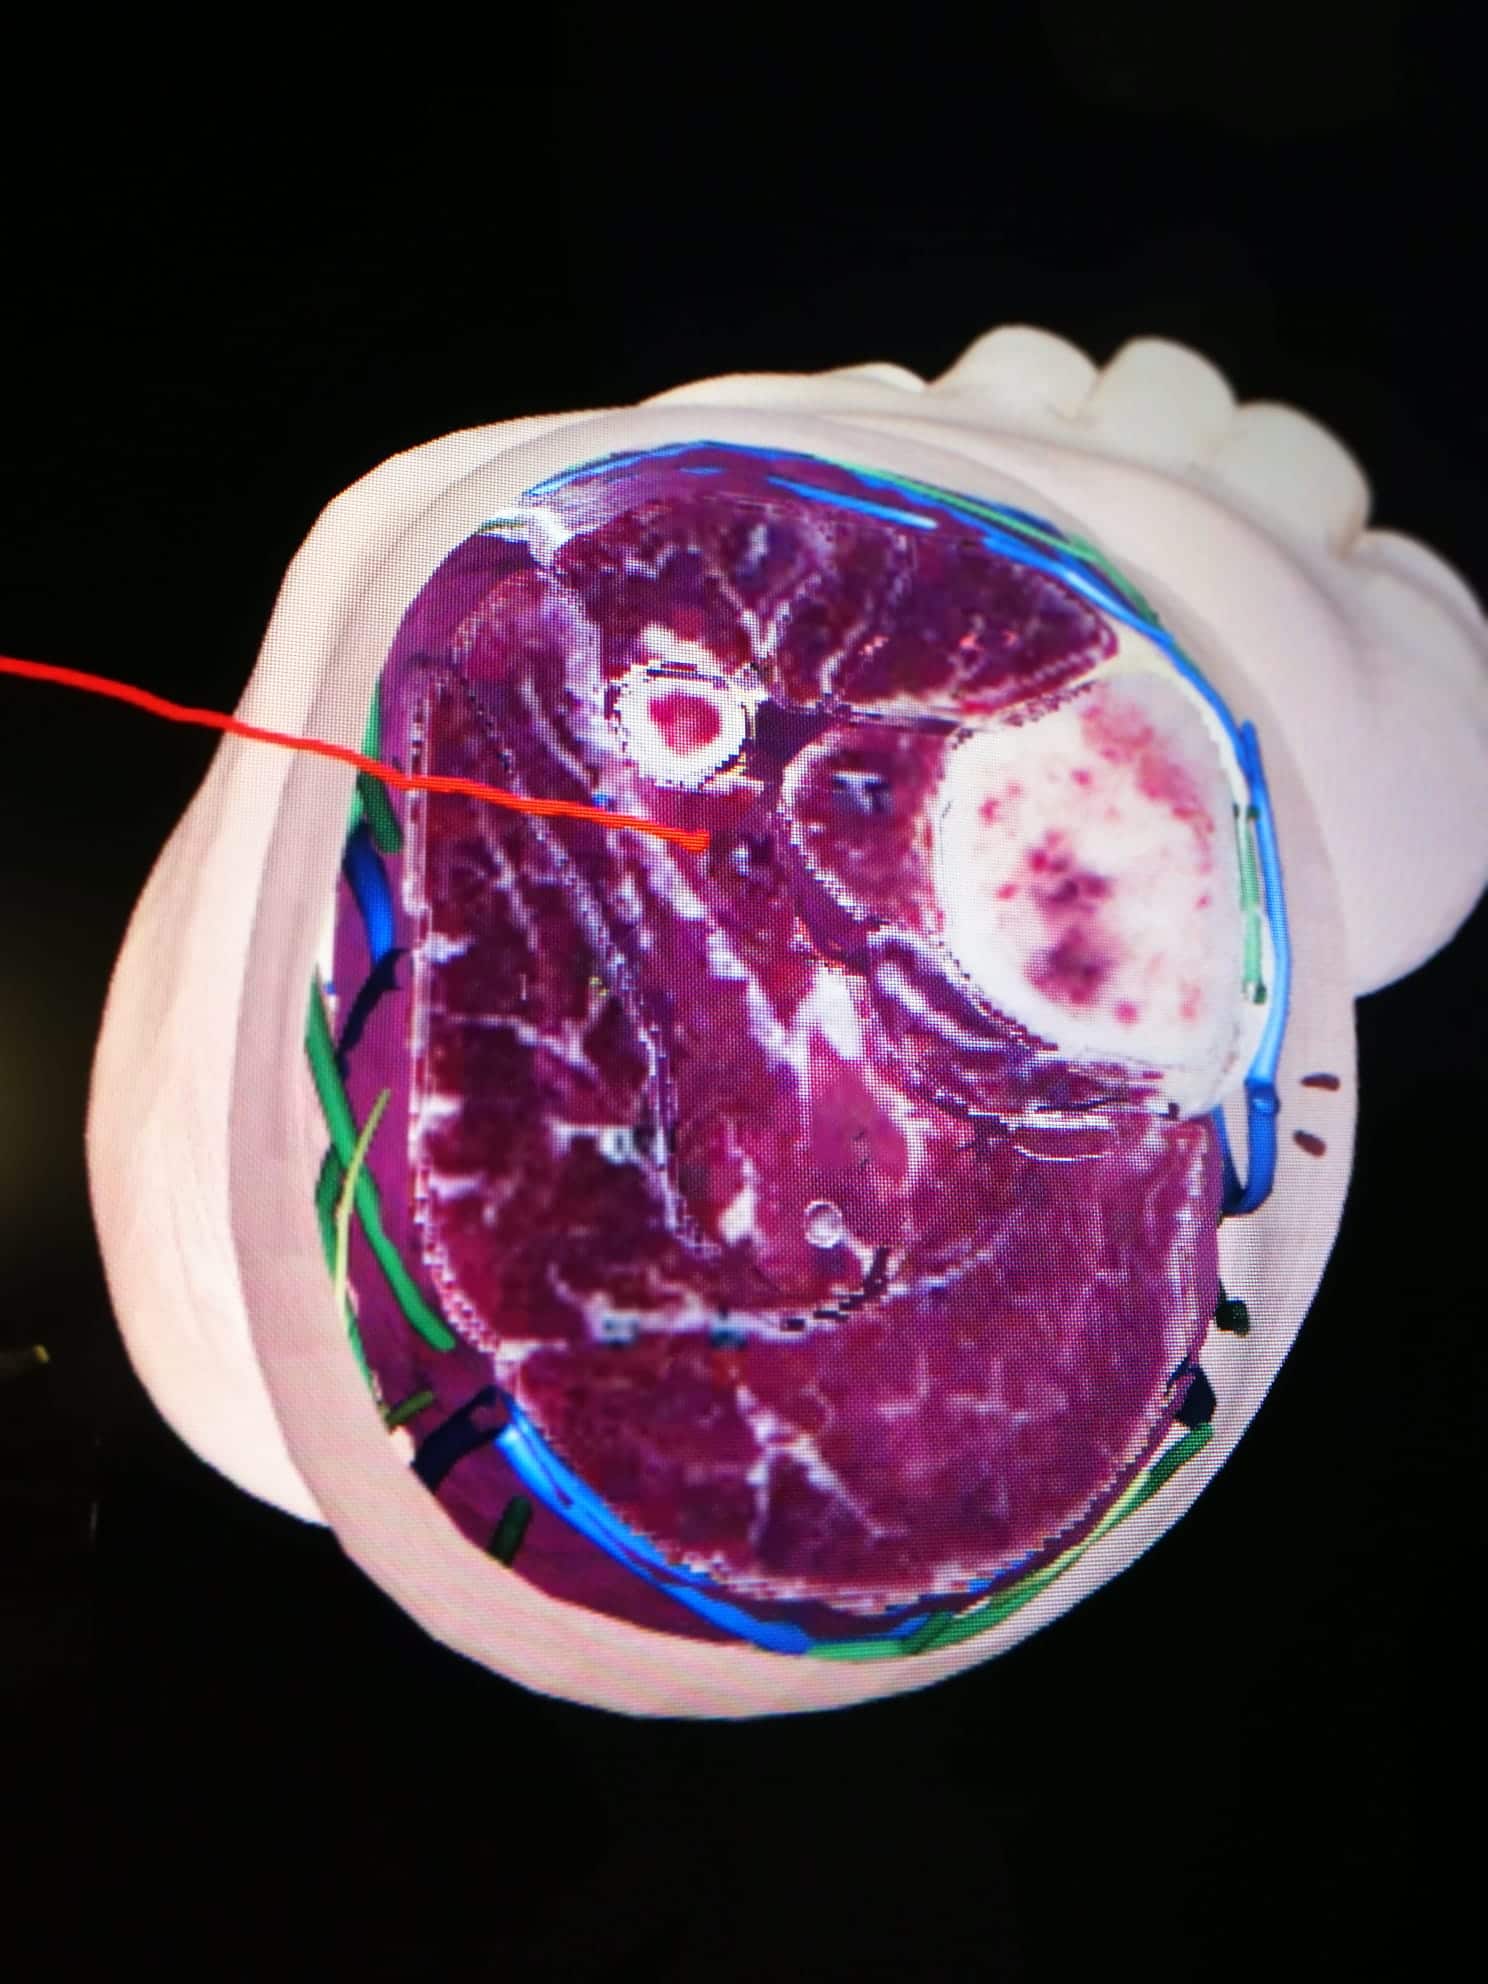

LUGAR: Av. de los Jerónimos, 135, 30107 Guadalupe (Murcia) – Sala de disección de la UCAM (Aulario 6)

DURACIÓN: 20 Horas

DOCENTES: Antonio García Godino, Manuel Moreno Más, Jose María Belmonte Hernández y Andrés Martínez Almagro

DIRIGIDO A: Fisioterapeutas y alumnos de fisioterapia